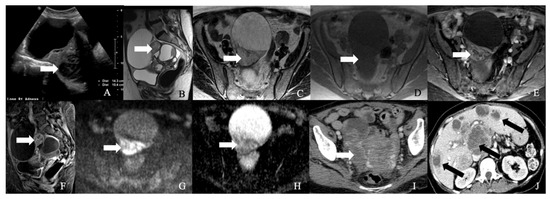

Figure 3. A 62-year-old female with neuroendocrine carcinoma of the cervix. (A) Sagittal T2 weighted image, (B) axial T2 weighted image, (C) oblique T2 weighted image, (D) axial pre-contrast T1 weighted image, (E) axial fat-saturated post-contrast T1 weighted image, (F) sagittal fat-saturated post-contrast T1 weighted image, (G) axial diffusion-weighted images (B-100), (H) axial apparent diffusion coefficient MRI images, and (I) Axial Ga-68 dotatate PET/CT image demonstrate a FDG avid enhancing mass in the cervix (arrow) with restricted diffusion and no parametrium involvement. The mass biopsy reported a small cell neuroendocrine carcinoma.

Cancers 14 01835 g003

Figure 4. A 52-year-old female with a neuroendocrine tumor of the cervix uteri. (A) Transverse and (B) sagittal ultrasound image of the cervix demonstrates a heterogenous cervical mass (arrow) measuring about 14 cm. (C) Sagittal T2 weighted image, (D) sagittal apparent diffusion coefficient map, and (E) sagittal fat-saturated post-contrast T1 weighted MRI images demonstrate a mass in the cervix uteri (arrow) with restricted diffusion. The mass biopsy reported a small cell neuroendocrine tumor of grade G3.